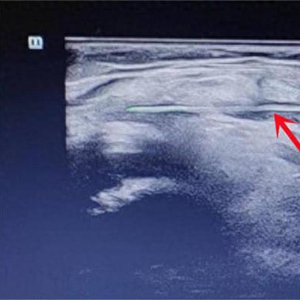

碰巧的是,淮安市第二人民医院超声医学科主任樊云清此时正在当地义诊,看到豆豆的右膝关节红肿,经验丰富的樊主任立刻就意识到一定是有异物刺入了膝关节,才会造成肿胀。在超声检查中,樊主任果然在豆豆的膝关节腔内发现一根针状物体,且关节腔内形成感染,并伴有广泛炎性积液,必须进行手术治疗,否则豆豆的膝关节将造成永久性损伤。

发现豆豆膝关节内有异物